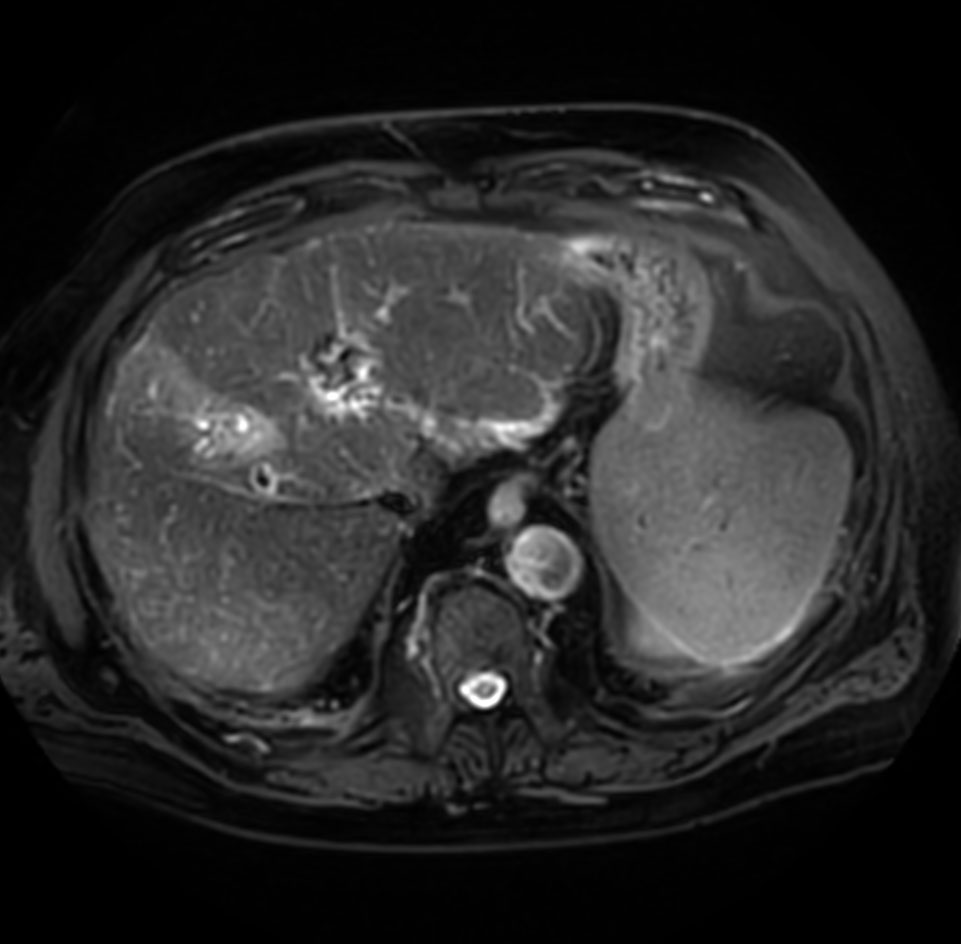

Axial T1w mDIXON XD (Out Phase)